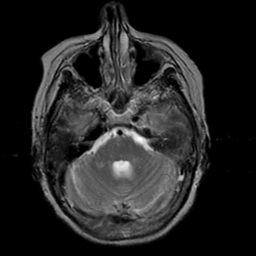

Stroke:T2-weighted MR #2 -- Slice #6

[Home][Help][Clinical] Slice 6